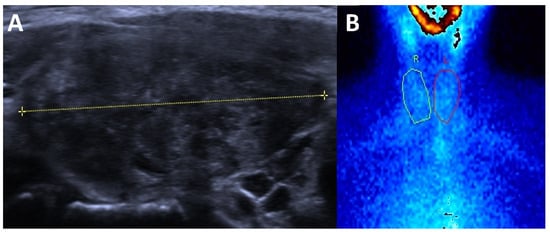

3.1. Hyperthyroidism

3.2. Hypothyroidism